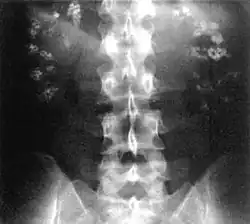

![]() Radiografía en la que se aprecia la existencia de depósitos de calcio en ambos riñones (nefrocalcinosis). | ||

En medicina, se denomina nefrocalcinosis a la existencia de depósitos de calcio en el parénquima del riñón que puedan detectarse mediante pruebas de imagen como radiografía o ecografía. No constituye una enfermedad en sí misma, sino un síntoma que puede deberse a diferentes causas, entre ellas el hiperparatiroidismo, la intoxicación por vitamina D y la acidosis tubular renal tipo I. Suele asociarse a elevación del nivel de calcio en sangre (hipercalcemia) y exceso de eliminación de calcio a través de la orina (hipercalciuria). Se detecta mediante pruebas de imagen, en la ecografía, por ejemplo, se aprecian los depósitos de sales de calcio localizados en diferentes partes del riñón como la médula renal y la papila renal.